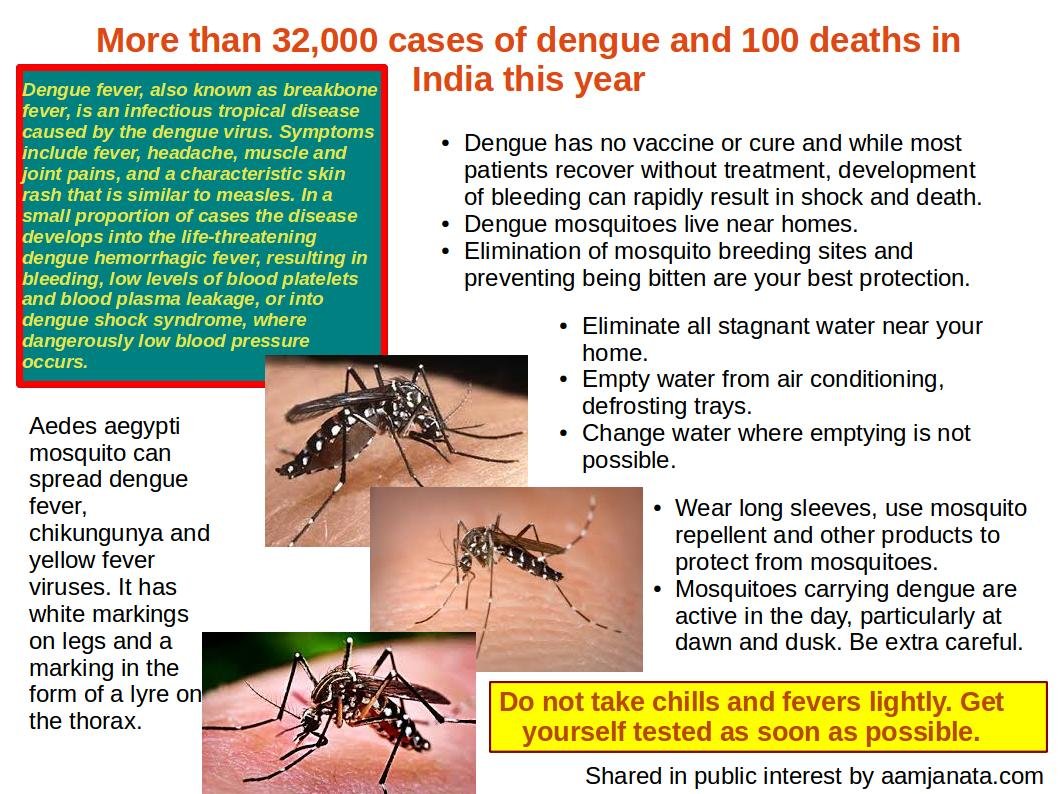

Cook Islands Dengue Fever Cases Rise to Four

Cook Islands Reports Four Dengue Fever Cases, Triggers Health Response RAROTONGA, Cook Islands – ...